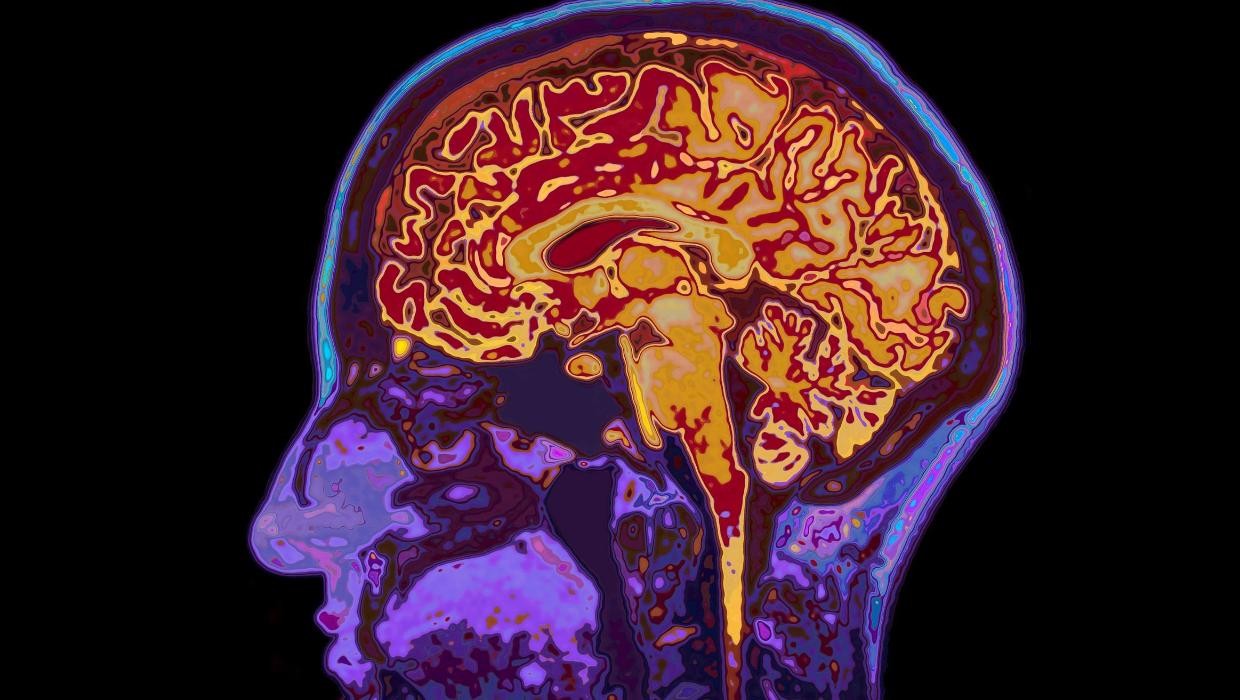

New Study Reveals Brain Development Stages Until Age 32

A recent study conducted by the University of Cambridge has unveiled significant insights into brain development, indicating that the human brain remains in a state of adolescence until the age of 32. The research identifies five distinct epochs of brain development and highlights four major turning points throughout a person’s life.

The study, led by Dr. Raffaella Rumiati and her team, reveals that brain maturation is a gradual process that extends well into early adulthood. This challenges the traditional notion that brain development concludes in the late teenage years. According to the findings, individuals continue to experience crucial cognitive and emotional developments until they reach their early thirties.